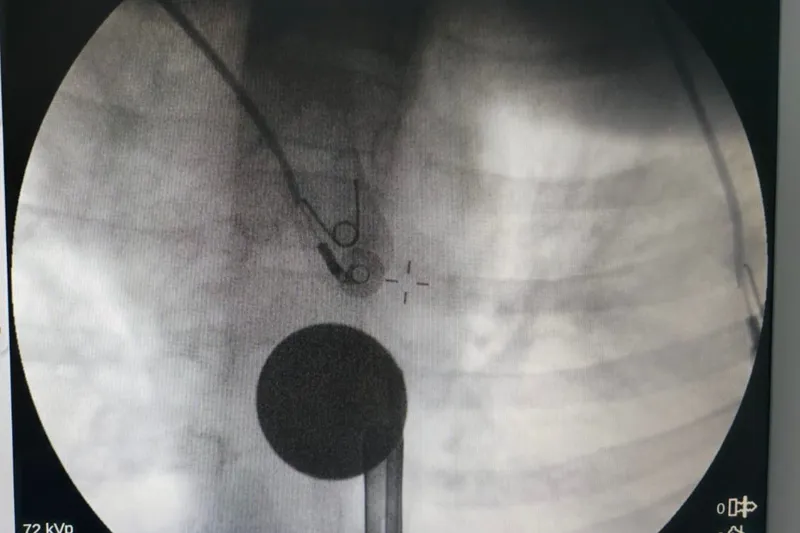

Gastroenteroloji ve KBB’den ortak operasyon

Madeni paranın çıkarılması için Gastroenteroloji Uzmanı Dr. Yaren Dirik ile Kulak Burun Boğaz (KBB) Hekimi Dr. Yasin Gökçınar tarafından ortak bir girişim gerçekleştirildi. Alanında uzman ekiplerin koordineli çalışmasıyla madeni para herhangi bir komplikasyona yol açmadan başarıyla çıkarıldı.

“Operasyon sorunsuz geçti, hastamızın durumu iyi”

Siirt Eğitim ve Araştırma Hastanesi Başhekim Yardımcısı Uzman Dr. Burak Özkan, operasyonla ilgili yaptığı açıklamada çocuklarda yabancı cisim yutma vakalarının hayati riskler taşıyabileceğine dikkat çekerek şunları söyledi:

“Hastanemize başvuran 8 yaşındaki hastamızın yemek borusuna kaçan madeni para, gastroenteroloji ve KBB ekiplerimizin koordineli çalışmasıyla başarılı bir şekilde çıkarılmıştır. Operasyon süreci sorunsuz geçmiş olup hastamızın genel durumu iyidir.”